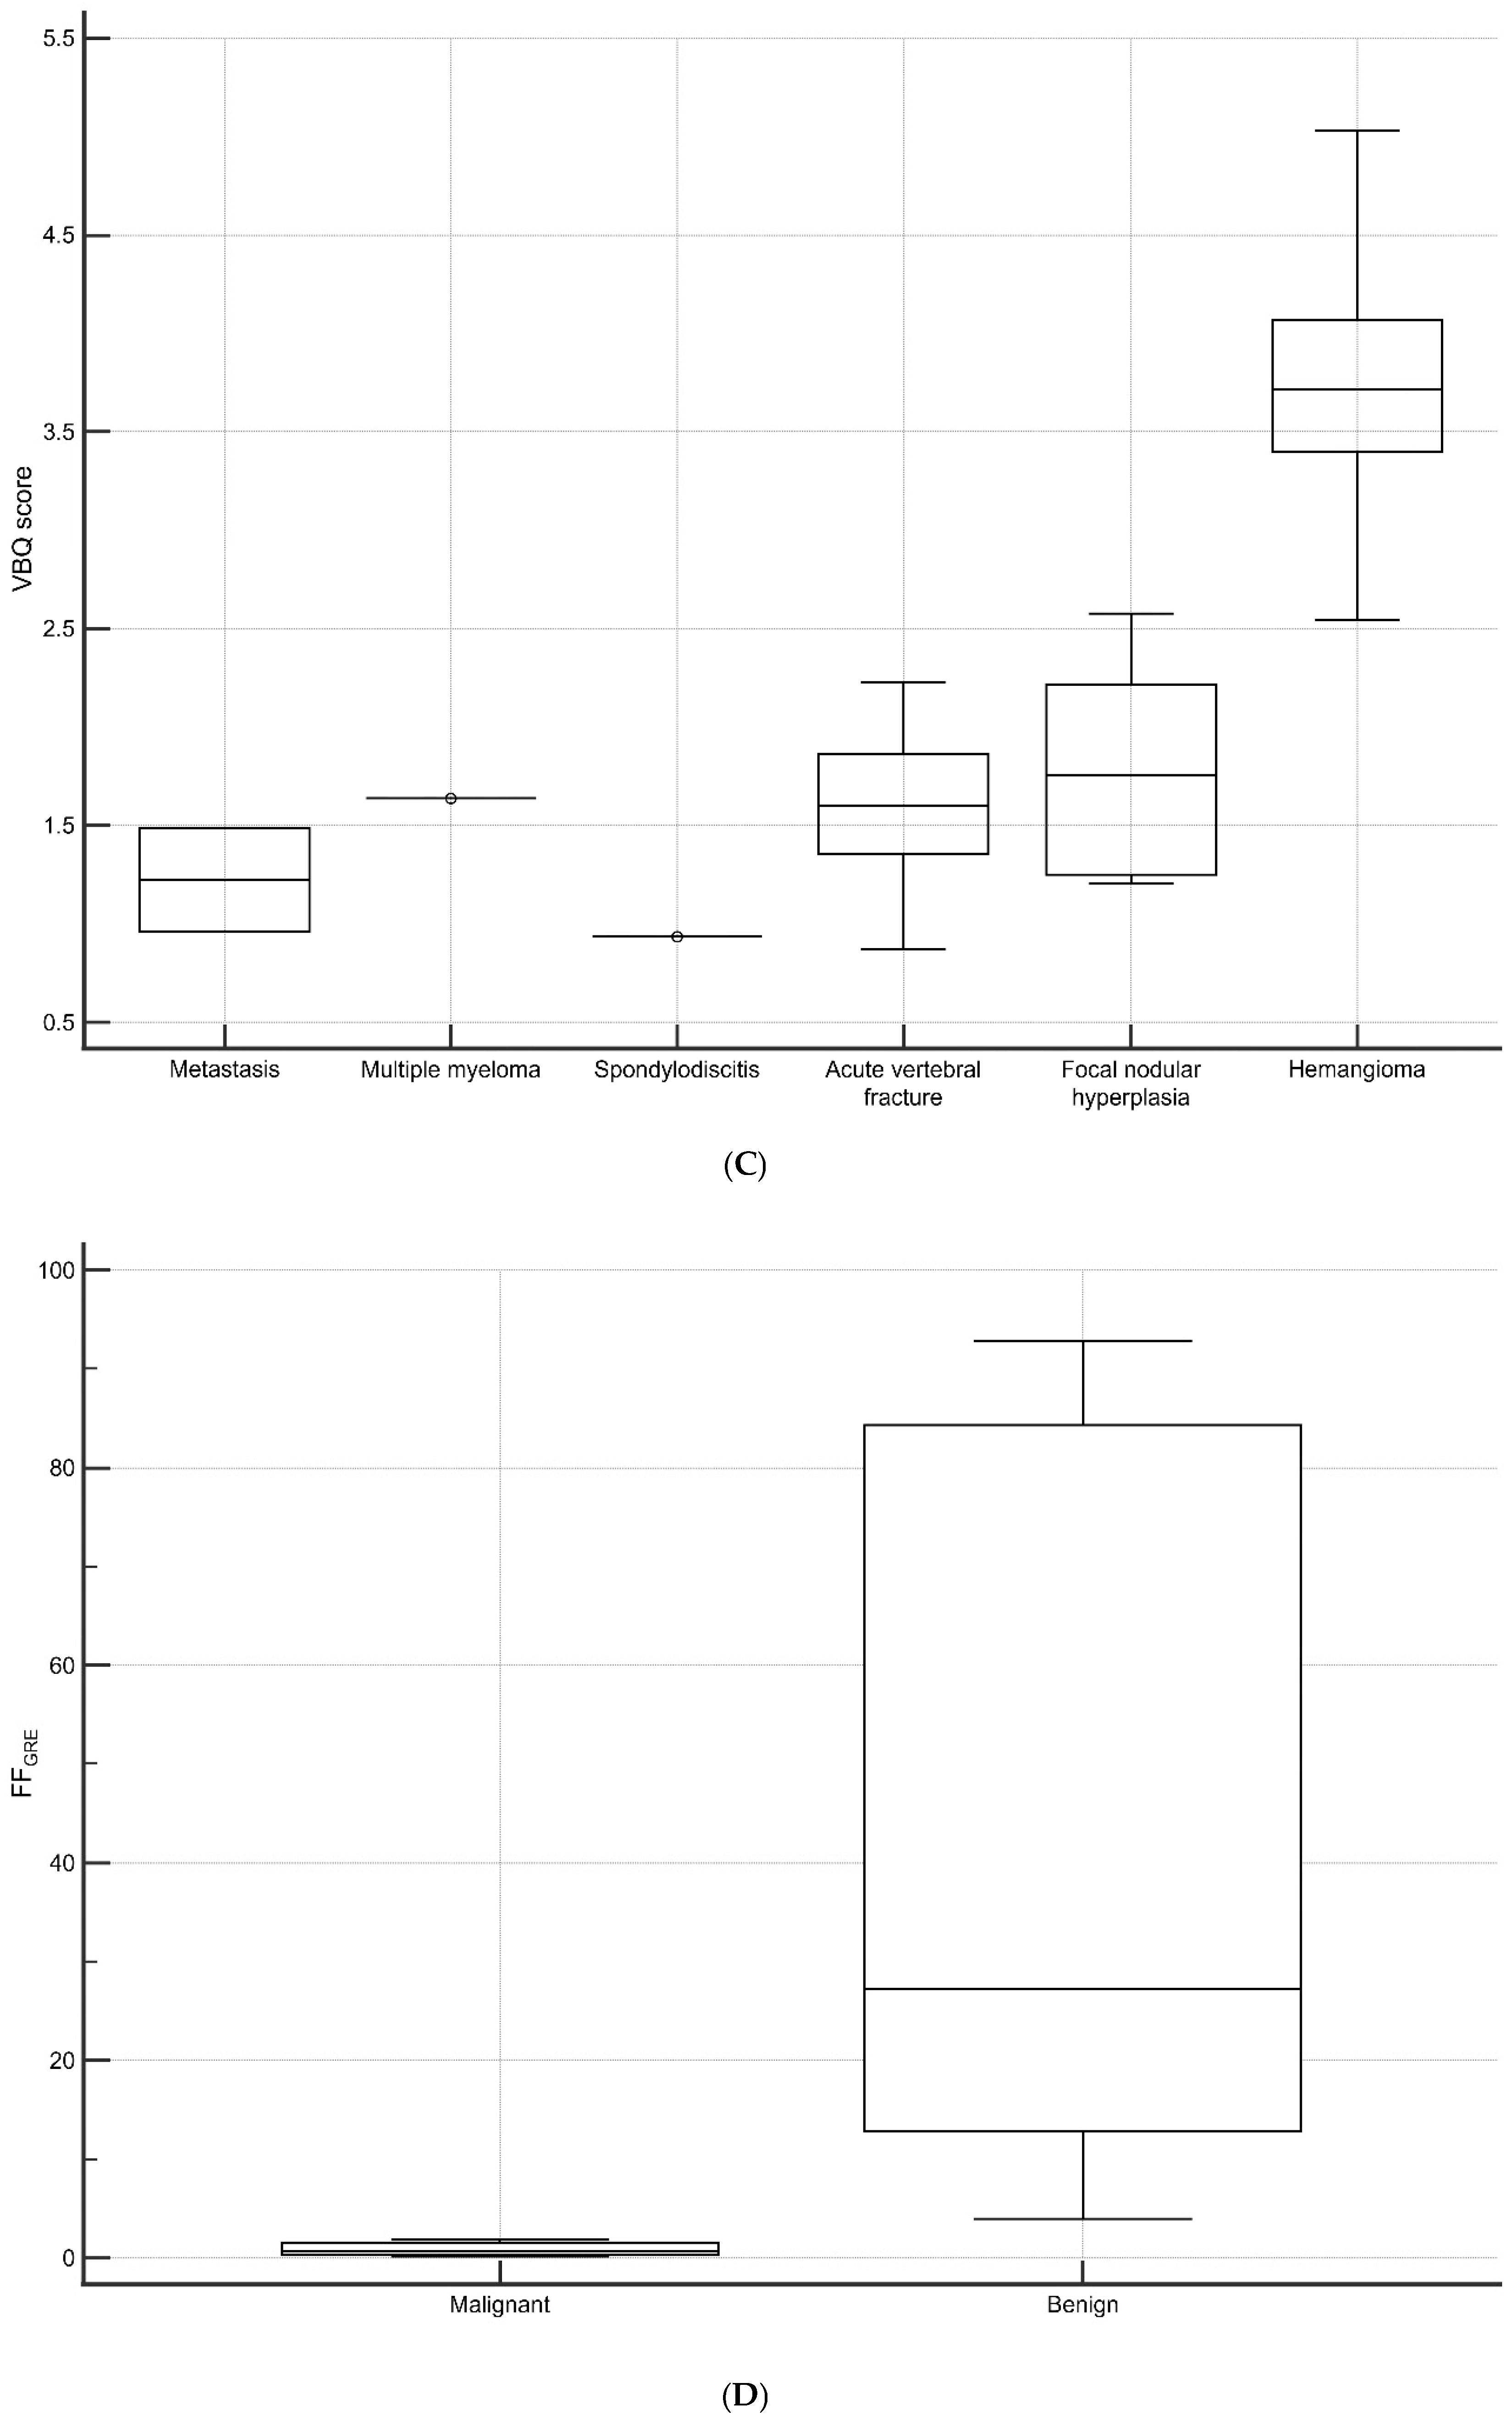

3.4. Vertebral Lesions Analyses